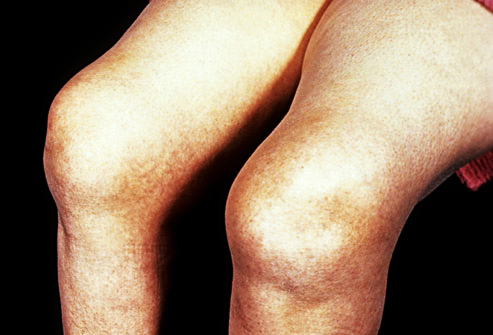

这张照片中的患者就是一个经历经过热敷以后积液没有吸收,反而越来越多的病例,大家可以看到他的膝关节皮肤上会有明显的地图上的改变,这都是长时间热烤的痕迹,患者特别的痛苦 。针对这个患者的病情,谢医生给予进行了关节穿刺抽取积液以后,告知患者适当的用药以及坚持冷敷,三周以后关节那滑膜炎的情况基本稳定,关节积液基本消失了。